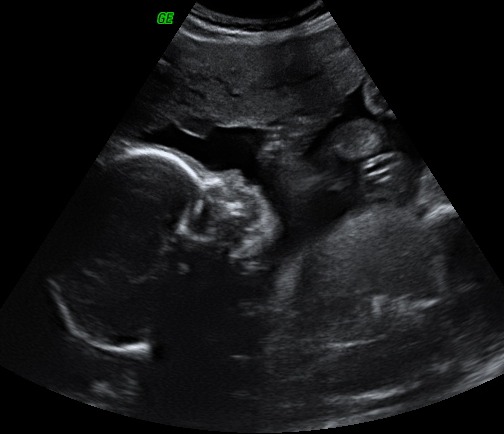

Ecografía de la semana 17 de embarazo: feto de perfil. Podemos observar a un bebé con una edad gestacional de 17 semanas. La imagen ecográfica nos muestra el corte sagital de la cabeza fetal de perfil. Se visualiza la órbita, la nariz y la boca. También se visualiza parte del abdomen y la placenta arriba de la imagen. En el líquido amniótico (en negro) se aprecia parte del cordón umbilical.